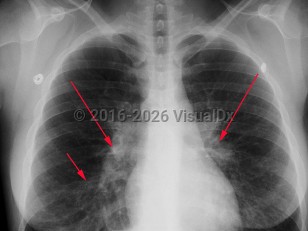

Mycoplasma pneumonia, also called atypical pneumonia and "walking pneumonia," is a community-acquired pneumonia caused by Mycoplasma pneumoniae. Mycoplasma are pleomorphic, filamentous bacteria that lack a cell wall, are of a smaller size, and possess different genetic features than other bacteria. Of all the Mycoplasma spp isolated from the respiratory tract, M pneumoniae is the most frequent cause of human disease.

Mycoplasma pneumoniae is a common cause of pneumonia and may be responsible for up to 20% of all pneumonias in the general population and 30%-50% of pneumonias in specific closed populations such as those in military barracks and on college campuses. Infection is most common in those younger than 20, although it is seen in all age groups. The disease is seen throughout the year, with a slight increase in incidence in the fall and winter.

Patients typically present with a dry, sometimes paroxysmal, cough; fever; headache; and malaise. They generally appear well to moderately ill and are rarely toxic appearing. Up to 50% of patients also present with upper respiratory involvement with a sore throat and earache. Hemorrhagic or bullous myringitis may be seen in those presenting with an earache. Mycoplasma exanthems frequently occur and can be a diagnostic clue.